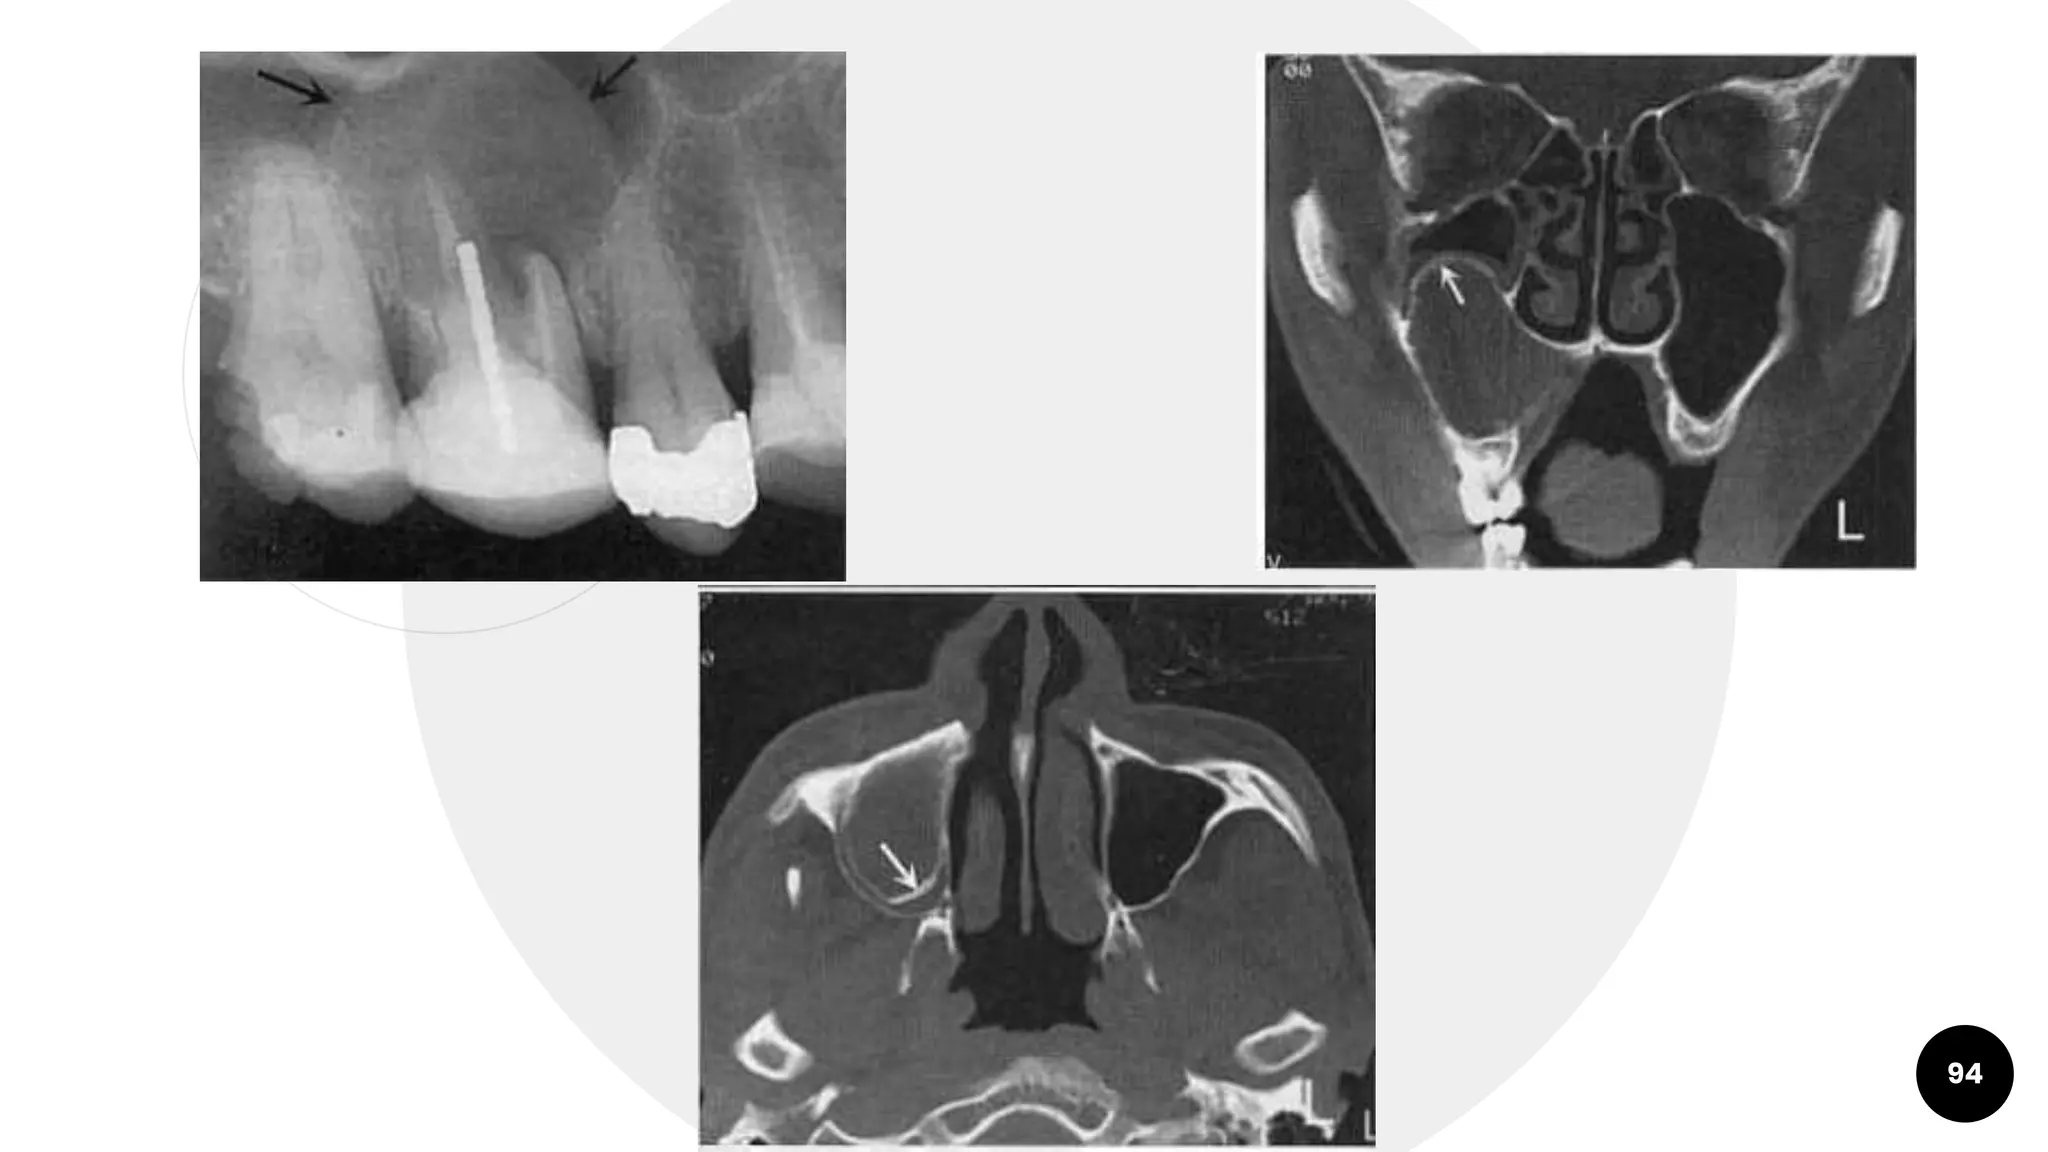

Radicular Cysts

○ Cause elevation of floor of

93

94